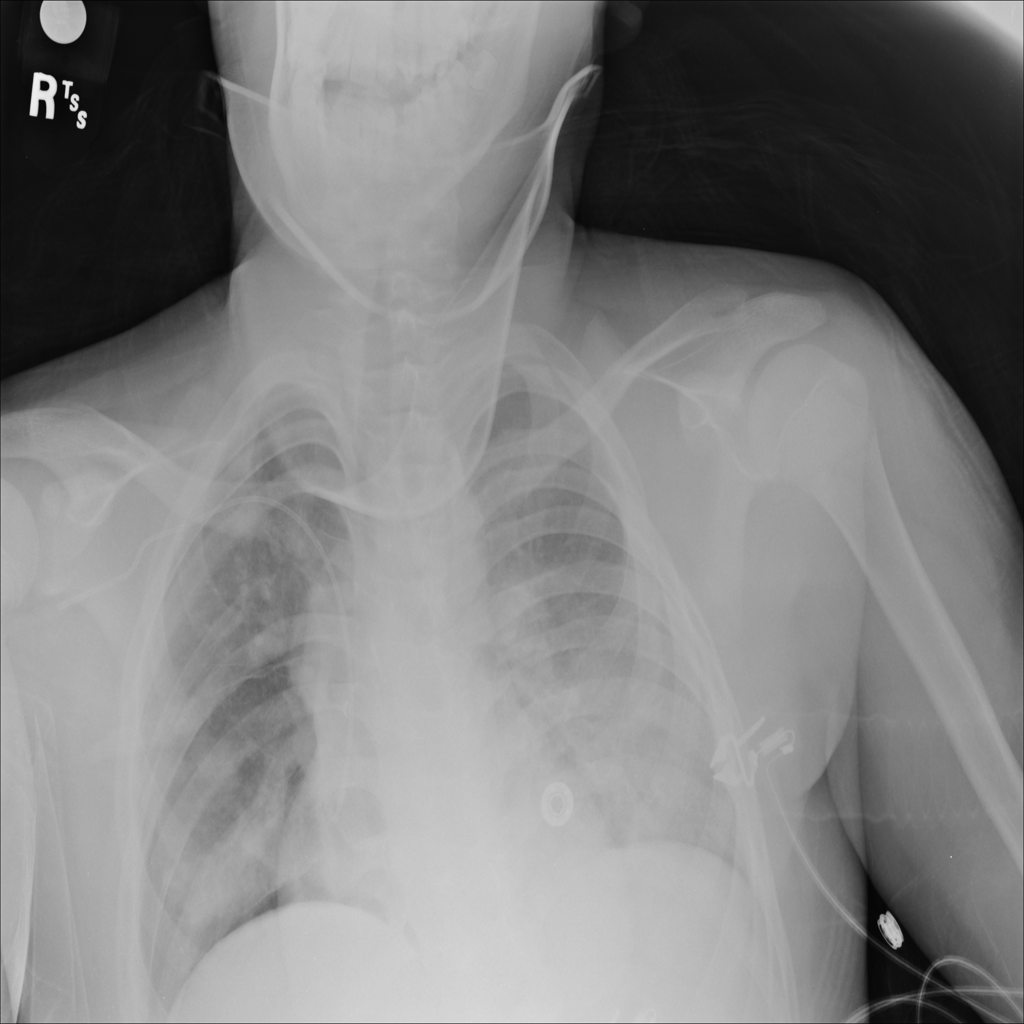

PAT-4639 · IMG-013Pneumothorax

PAT-4639 · IMG-013

AP